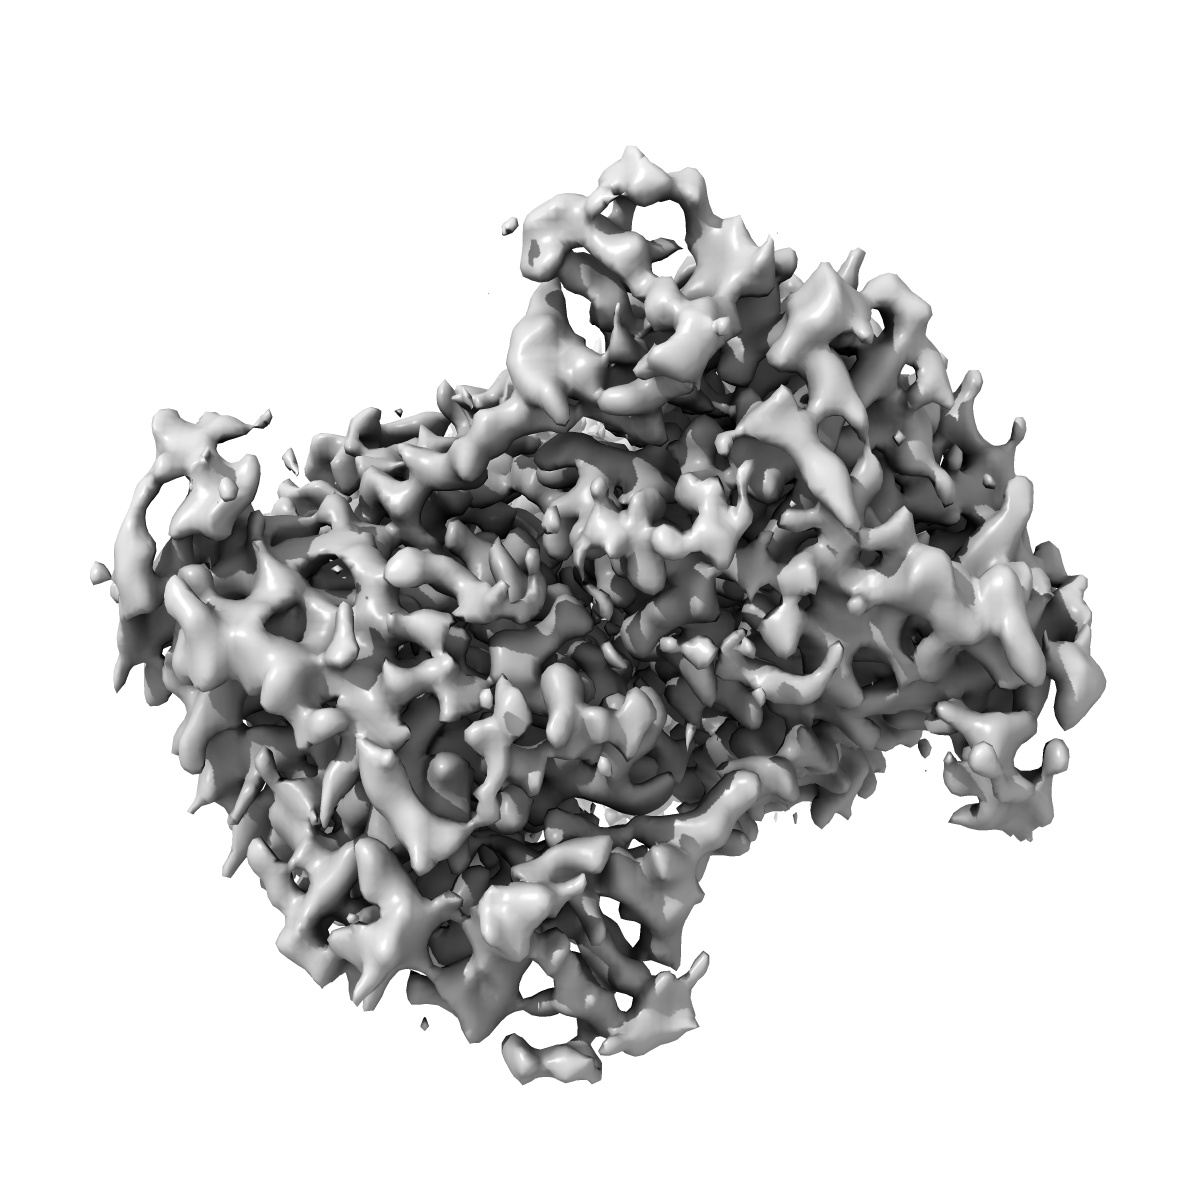

Raw Consensus map of the Calcium-Sensing Receptor in complex with positive allosteric modulator '54149

Sample: Calcium-sensing receptor bound to compound '54149

Large library docking identifies positive allosteric modulators of the calcium-sensing receptor.

Liu F , Wu CG , Tu CL, Glenn I, Meyerowitz J, Kaplan AL , Lyu J , Cheng Z, Tarkhanova OO , Moroz YS, Irwin JJ , Chang W , Shoichet BK , Skiniotis G

(2024) Science , 385 , eado1868 - eado1868